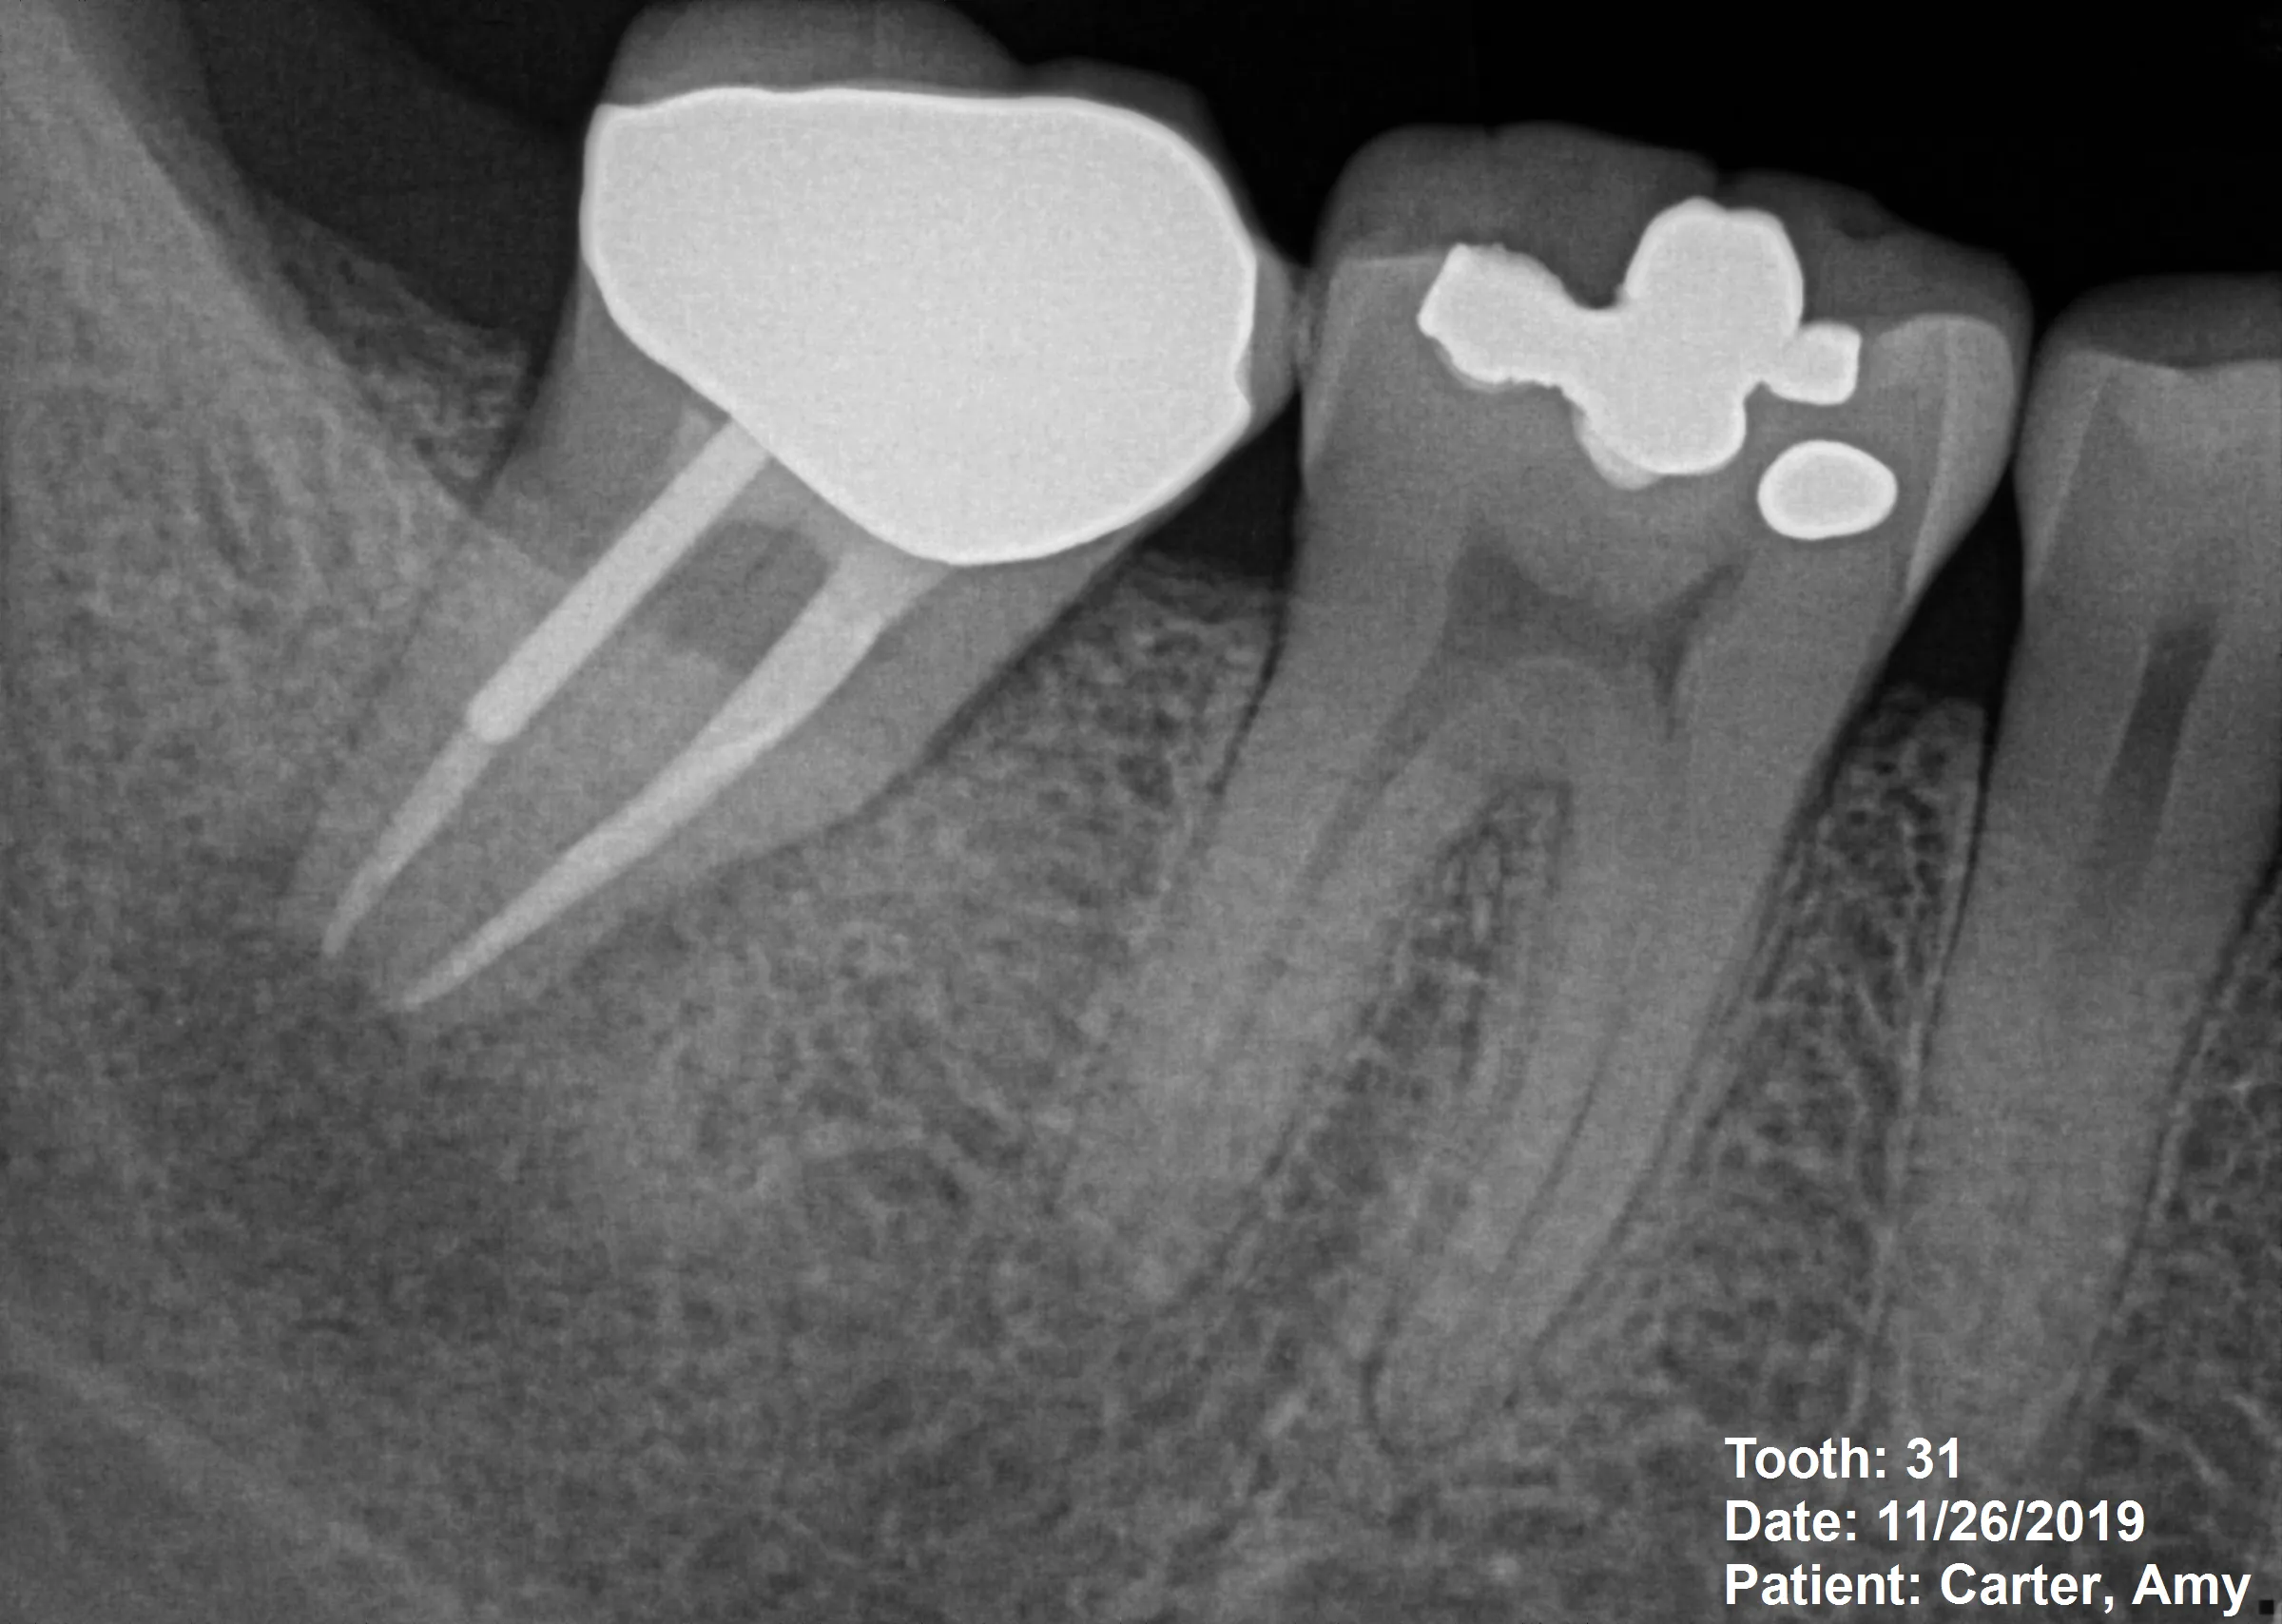

Intentional Reimplantation — Saving a Molar When Retreatment Fails

2 Appointments Extreme Difficulty 12 Months Follow-up

CBCT Analysis Atraumatic Extraction Intentional Reimplantation MTA Retrofill

54-year-old Palos Verdes patient with sudden severe pain in lower mandibular molar

Previous root canal treatment failing, with large metallic post blocking orthograde access

Atraumatic extraction with ultrasonic apical preparation and MTA retrofill, followed by immediate reimplantation

1. CBCT Imaging: Essential for evaluating root morphology, planning extraction approach, and identifying anatomical obstacles

• Radiograph: Immediate postoperative film to document position

Patient Outcome in This Case

At 12-month recall:

• Complete resolution of pain and periapical symptoms

• Radiographic evidence of bone regeneration around apical region

• CBCT confirms healing of periapical lesion

• Tooth asymptomatic to percussion and palpation

• Normal function—patient reports no limitations

• No evidence of root resorption